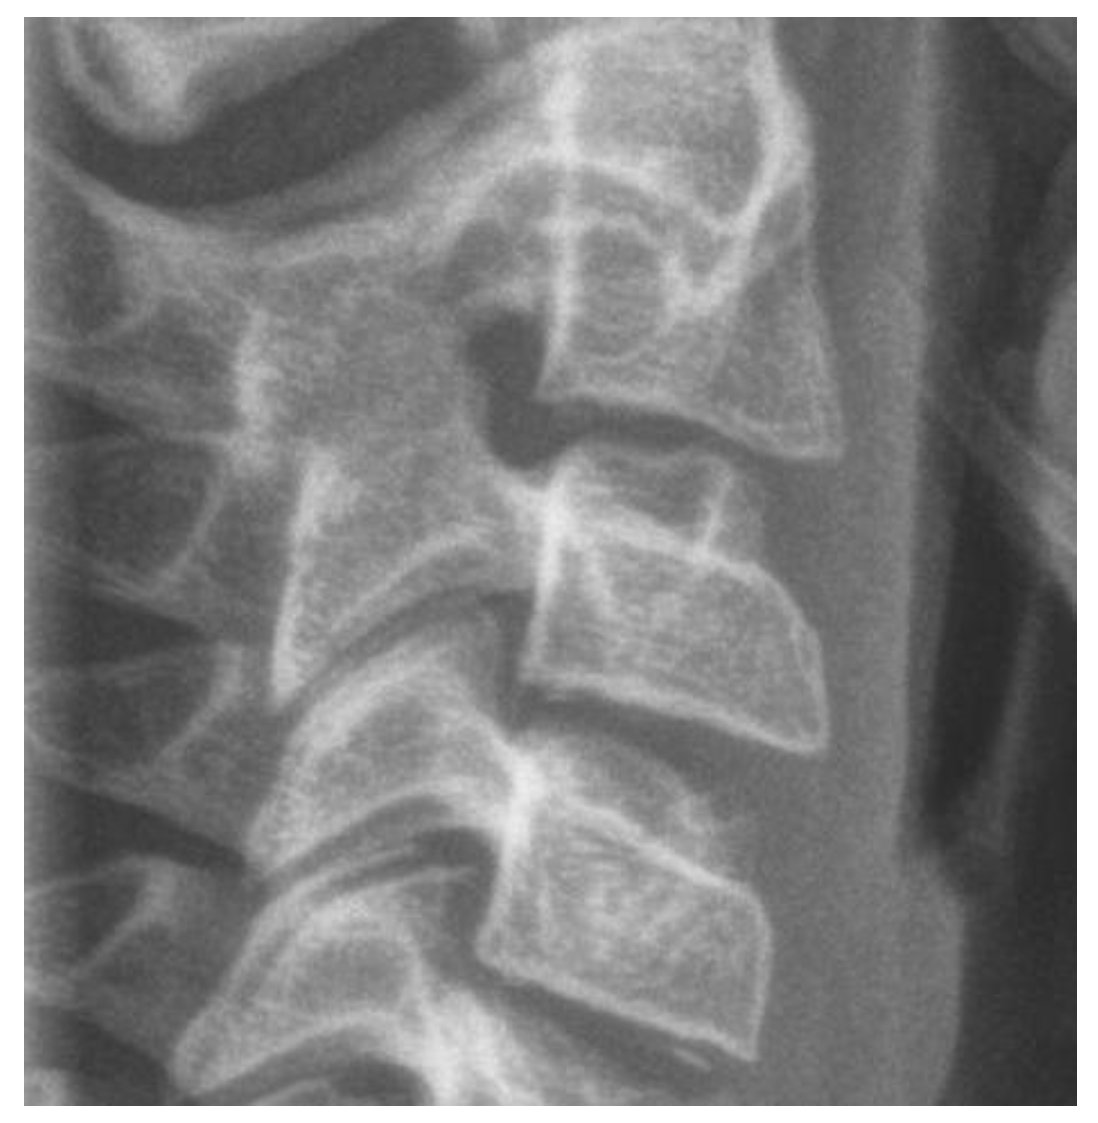

3.3.2. Cervical Vertebrae Radiography